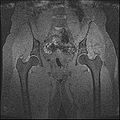

The aim of this project is to develop a methodology for rapid segmentation of knee structures from magnetic resonance (MR) images for subject-specific modeling. The overall goal can be broken down into two specific objectives -

Objective 1: We have adopted a multi-contrast MR methodology to segment knee bones and cartilage structures. The algorithm utilizes tissue intensity information from multiple MR contrasts to segment structures of interest. Inputs to the algorithm included n registered MR image sets. The algorithm created an n-dimensional space of voxel intensities associated with the n image sets. The user assigned seed points to the structures of interest, and the algorithm created a cluster center for each structure of interest. Cluster radii were calculated based on standard deviations obtained from seed points, and tissue structures were classified as label maps.

• Generated label maps of knee and hip structures.